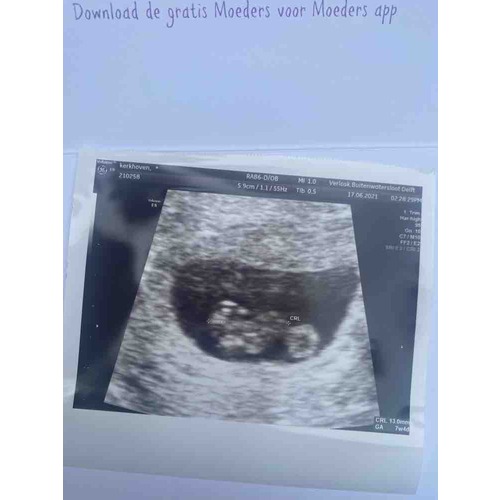

dit was bij mij met 8 weken, zie je ook niet erg veel in nog als je het mij vraagt

dit was bij mij met 8 weken, zie je ook niet erg veel in nog als je het mij ...

Nee maar het ik vind dit ook geen zeepaardje! Dit is wel gewoon breed en vol zeg maar.